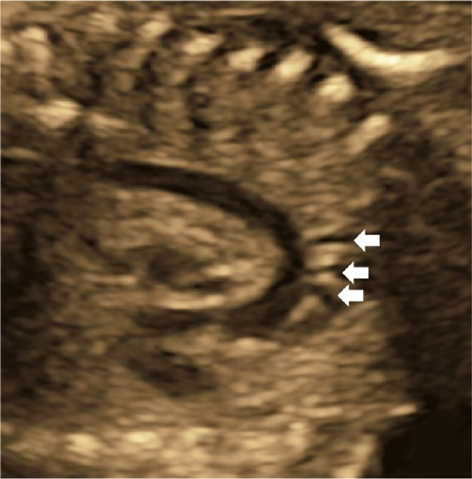

Coarctation of the aorta is difficult to diagnose in the absence of other structural abnormalities of the heart. It is to be suspected when; the aortic isthmus diameter Z score ≤−2.0, the ratio of the diameter of the ductus arteriosus to that of the aortic isthmus ≥1.5, continuous or retrograde blood flow present in the aortic isthmus, a posterior shelf obvious at the aortic isthmus, or structures of the left heart small.57)